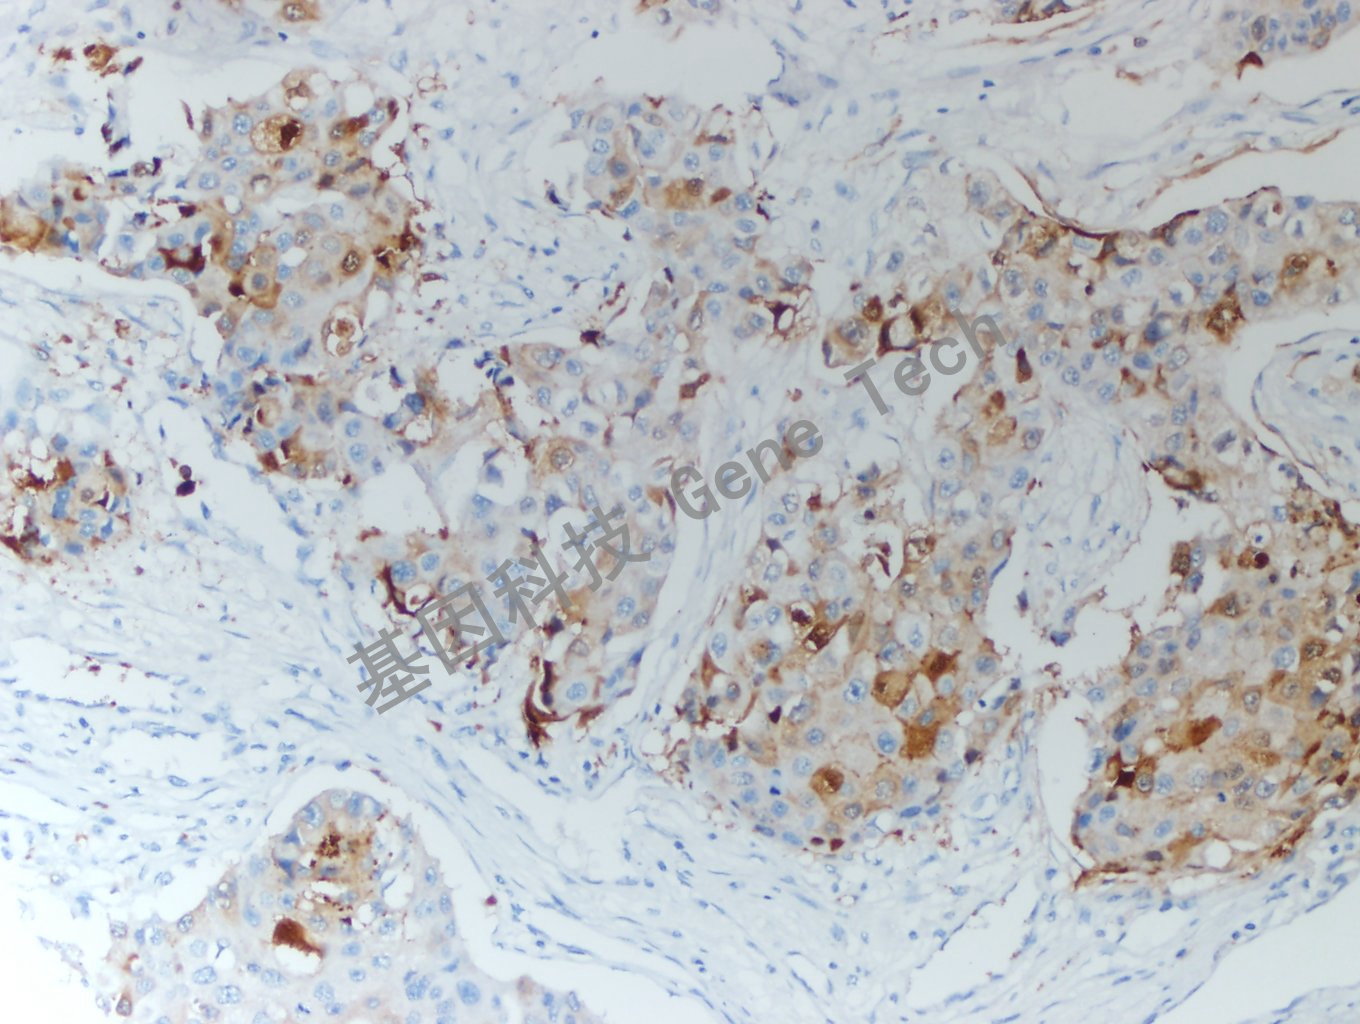

乳腺癌石蜡切片,用 HIF-1α(GT2377)染色,细胞浆/细胞核阳性,DAB 显色。